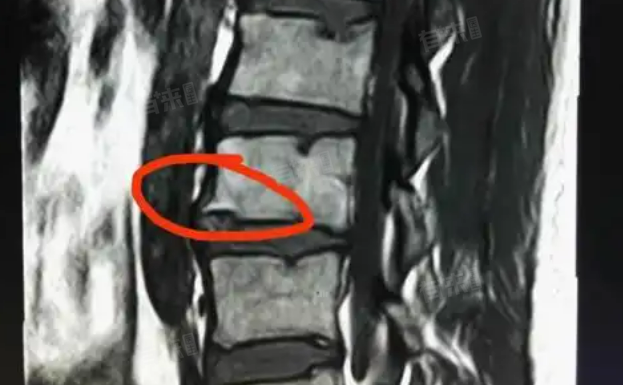

许莫氏结节是椎体软骨板破裂,髓核经裂隙突入椎体内形成,其治疗依病情而异,轻度者多保守治疗,严重或伴其他问题则可能需手术干预,以减轻不适症状。

对于无症状或症状轻微的许莫氏结节,通常无需特殊治疗,定期进行X光、CT或MRI检查,观察结节变化及椎体情况。日常生活中保持良好姿势,避免过度负重与剧烈运动,防止结节进一步发展,多数患者可正常生活不受限。